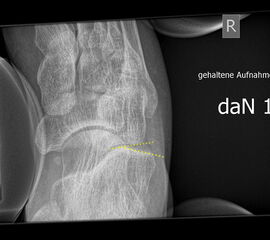

Stressaufnahmen oberes Sprunggelenk

Indikation:

• Beurteilung von (chronischen) Kapsel-Band-Instabilitäten am oberen Sprunggelenk. Wichtig ist, dass der Patient bei der Aufnahme nicht anspannt 171819.

• In der Beurteilung von akuten Verletzungen hat die gehaltene Aufnahme ihre Bedeutung verloren. Durch schmerzbedingtes Gegenspannen ist meist keine Aussage möglich.

• Die Aufnahme ist nur beim schmerzfreien Patienten verwertbar.

• Eine vermehrte Aufklappbarkeit/Talusvorschub ist beweisend für eine Kapsel-Band-Laxizität oder Bandruptur, allerdings können die Aufnahmen falsch-negativ sein.

Stressaufnahme des oberen Sprunggelenks lateral

Position:

• Patient in Seitenlage auf dem Röntgentisch, zu untersuchender Fuß unten und seitlich auf der Röntgenkassette liegend (Achse des Fußes parallel zum Zentralstrahl).

• Zentralstrahl mittig auf das obere Sprunggelenk fokussiert.

• Film horizontal auf dem Röntgentisch.

• Röntgenröhre 0° vertikal.

• Der Fuß liegt in der Haltevorrichtung (z.B. Telos-Gerät, Scheuba-Apparat). Die Ferse wird von dorsal stabilisiert.

• Von ventral wird über die Tibia ein kontrollierter Druck von bis zu 15 daN (Dekanewton, entspricht ca. 15 kg) aufgebaut.

Kennzeichen des Röntgenbildes:

• Laterale Abbildung des oberen Sprunggelenks.

• Beurteilung der Translokation des Talus nach ventral (Talusvorschub).

• Gemessen wird die Verschiebung der Tibiaachse gegenüber der Talusachse.

• Als pathologisch gelten Talusvorschub > 2 mm im Seitenvergleich oder absoluter Talusvorschub > 4 mm.

Besondere Bemerkungen zum Beispielbild:

• Abbildung des oberen Sprunggelenks lateral.

• Fremdkörper in den plantaren Weichteilen in Höhe der plantaren Begrenzung des Kalkaneus.

Anmerkung:

• Belastungsaufnahmen können sowohl manuell gehalten, als auch mit verschiedenen Hilfsgeräten durchgeführt werden. Standard ist eine Druckapplikation von 15 kp. In der akuten Verletzung ist eine Stressaufnahme nur unter Analgesie (z.B. Lokalanästhesie des Kapsel-Band-Apparats) aussagekräftig. Für den Behandlungsalgorithmus nach Außenbandverletzung spielt die gehaltene Aufnahme heute nur noch eine untergeordnete Rolle. Bei unklaren Befunden ist ein Vergleich mit der Gegenseite möglich; dieses zwangsläufig mit einer höheren Strahlendosis belastete Vorgehen sollte aber nicht zur Kompensation mangelnder röntgenmorphologischer und anatomischer Kenntnisse verwendet werden.